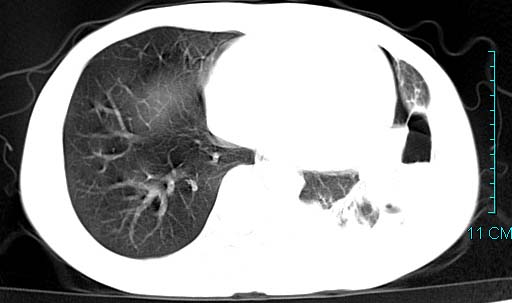

以下是引用qian在2006-3-28 14:32:00的发言:[br]左肺下叶大片状阴影,密度不均,见有条片影和空洞及气液平,少量胸腔积液伴有胸膜增厚,从图像看积液密度比水的密度高,结合病史,考虑左下肺化脓性炎症伴有脓胸。

以下是引用wawaquan在2006-3-28 22:25:00的发言:[br]左上肺舌段多发斑片影。结合“男24y咳嗽咳痰气促伴高热(38.5--39.5)20多天”及穿刺史,[br]考虑1 左下肺化脓性炎症;2脓胸。

以下是引用乡医在2006-3-28 18:37:00的发言:[br]左侧多发液气平面结合患者男24y咳嗽咳痰气促伴高热(38.5--39.5)20多天,查胸水:ldh239.3,总蛋白59.19,tb-ab阴性,利凡它试验+,红c2.7*109,白c1.08*109,分类淋巴92%分叶8%,考虑1脓胸2肺隔离征感染